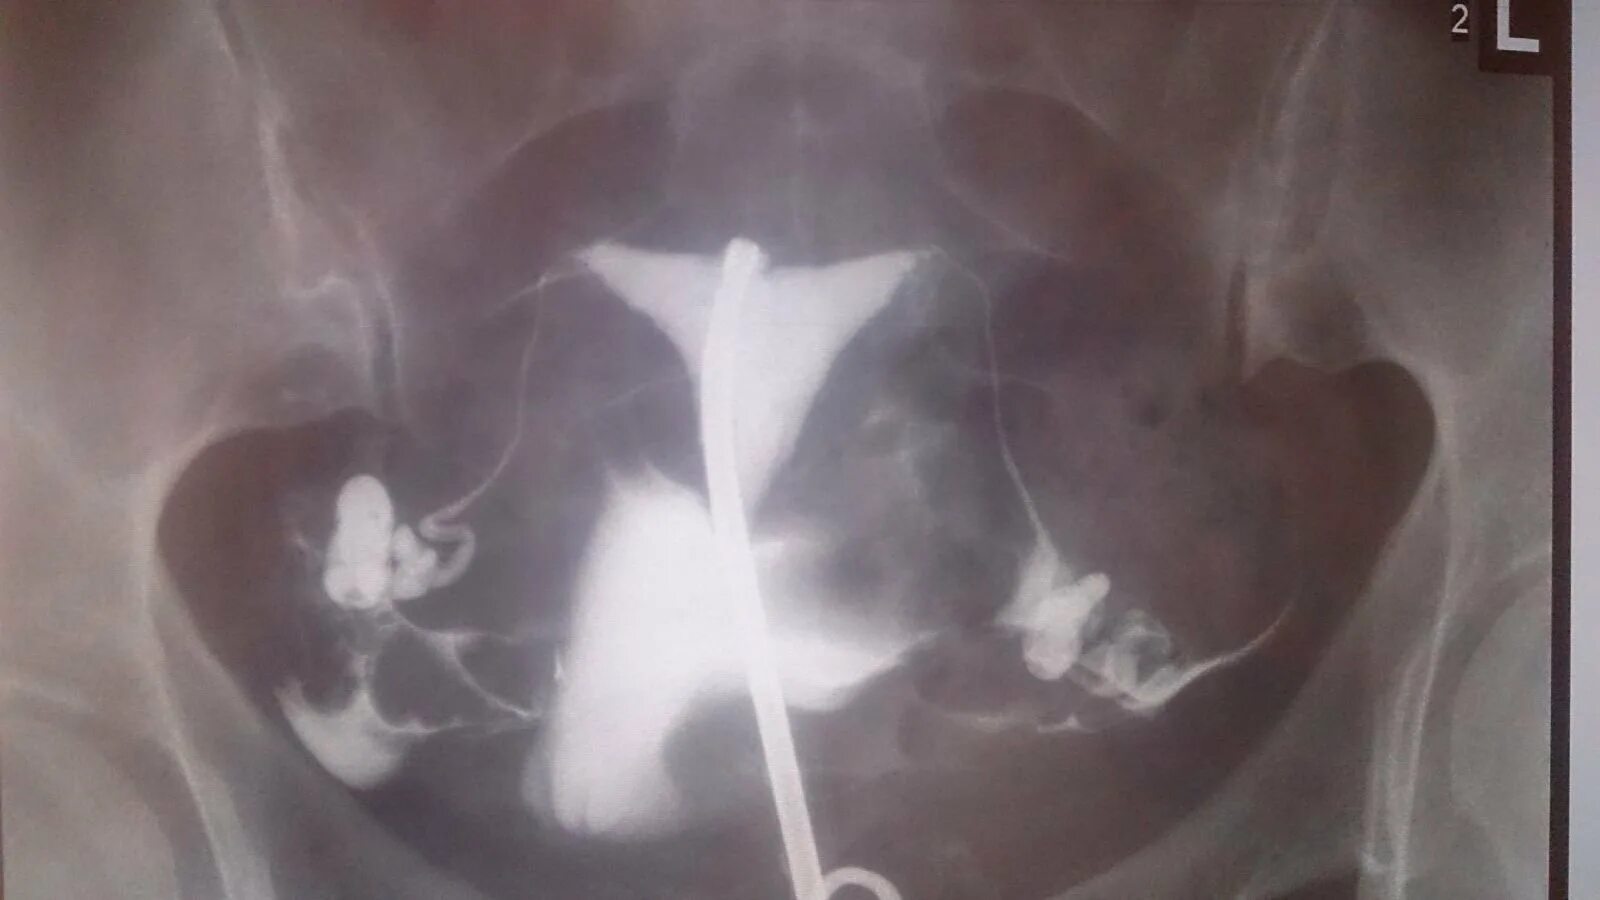

Проходимость маточных труб форум